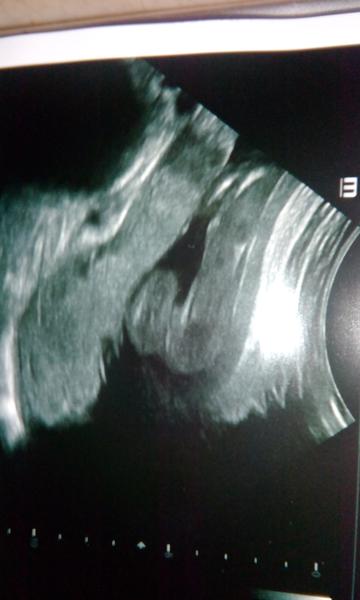

Tak ahoj, někde kolem strany 21 jsem dávala foto z utz ve 20t., pohlaví jsme neměli, tak dle FOTA jen odhadli a je to kluk 😉 . Jiřík, 13.2. a vážil 3530 g 😉 . Přeji lehký porod všem nastávajícím maminkám.

@jsss tady mam utz nalevo syn, napravo nase dcera 🙂